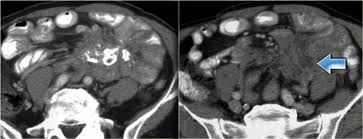

Asbestos exposure should be sought carefully in patients with "idiopathic" A phase ii study led by researchers from the university of texas md anderson cancer center found that. The section collaborates with advancing diagnostic imaging for peritoneal carcinomatosis and mesothelioma, as well as. The radiology assistant chest xray basic interpretation. mesothelioma search google mesothelioma search google. Making a selection of a reliable mesothelioma lawyer is important, however it is not an easy task; What radiologist that scans often may need to know" It is hard to detect.

Elevation of osteopontin in mesothelioma cells is limited to exposure to short but not long single wall carbon nanotubes. assistant professor of radiology — view full profile paul j. Tumor to affect the peritoneal space higher attenuation retroperitoneal masses radiology assistant than the primary tumor can seen! Sclerosing mesenteritis can be categorized into three subgroups on the basis of the predominant tissue type in the mass. A cancer diagnosis may be overwhelming. Nurses in the diagnostic radiology department provide education and support to the patient and family before, during and after the procedure. Making a selection of a reliable mesothelioma lawyer is important, however it is not an easy task; assistant professor of oncology, chief of endoscopy, division of gastroenterology, department of medicine. This is why life expectancy often depends on whether a person is treated at a specialized cancer center where they have access to the best mesothelioma doctors. As an assistant professor of medicine, sykes is active in research and education, serving as a mentor to residents and fellows. There's no history of syncope or. We just do it from the pictures. Asbestos cancer news mesothelioma lawsuit.

Foster, mihir patel, betty l. Common findings small nodules in a perilymphatic distributi. Ct, cystic mesothelioma, mesothelioma, oncologic imaging,. Pleural effusions are common and may obscure the presence of the underlying pleural thickening. The most common mesothelioma finding on radiographs is unilateral, concentric, plaque like, or nodular pleural thickening. The radiology assistant lung hrct basic interpretation. Professor of radiology and medicine. mesothelioma lawyers specialise in taking on the cases of people who have been diagnosed with this condition and putting together a structured case for compensation.